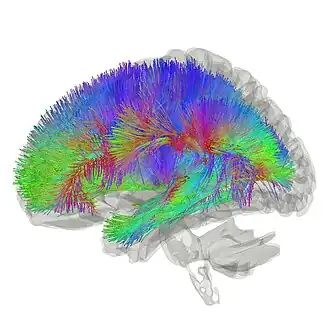

Tractography of thalamocortical radiations | |